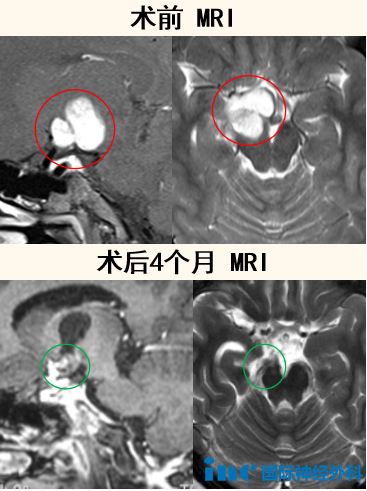

孩子偶然的头晕,背后竟隐藏着一个十分“难缠”的胶质瘤,盘踞在脑干中脑脚部,延伸至右侧下丘脑,并向上延伸至丘脑。脑干、丘脑,这两个素来被认为是“手术禁区”的危险地带,却因肿瘤双双“沦陷”,其中涉及的神经、血管数不胜数,却都是关系着患儿生命的重中之重。

7岁的秋秋由于阵发性的头疼、头晕而被当地医院诊断出“鞍区病变”,医生建议进行活检以明确诊断。于是,10天后秋秋接受了右侧丘脑的“立体定向颅内肿物清除术”,术后病理报告提示该肿瘤为神经上皮性肿瘤,分子检测提示符合毛细胞星形细胞瘤(WH01 级)。

好在是低级别胶质瘤,秋秋父母不禁松了一口气,医生也告诉他们这种肿瘤一般全切预后较好,然而,问题也接踵而至:肿瘤偏偏长在了脑干中脑-丘脑这两个“手术禁区”上,想要安全切除非常困难。

正是因为巴教授丰富的脑干手术经验,最终秋秋的手术在苏州大学附属儿童医院神经外科团队的协作下获得成功,肿瘤得到令人满意的切除。

在术后5个多月的随访中,教授表示秋秋在该位置的神经功能表现良好,整体神经功能令人满意。虽然如同术前教授预估,由于肿瘤靠近皮质脊髓束,术后秋秋出现了轻微的左侧肢体无力,但由于儿童大脑的可塑性很强,巴教授认为即使术后恢复过程可能持续超过一年,也有实现完全或几乎完全恢复的可能性。因此,针对后续的治疗,教授建议秋秋可以进行专门的儿童康复理疗,这将有助于加快康复进程,但目前秋秋无需进行辅助治疗,而应该以孩子的功能状态逐步恢复为主。